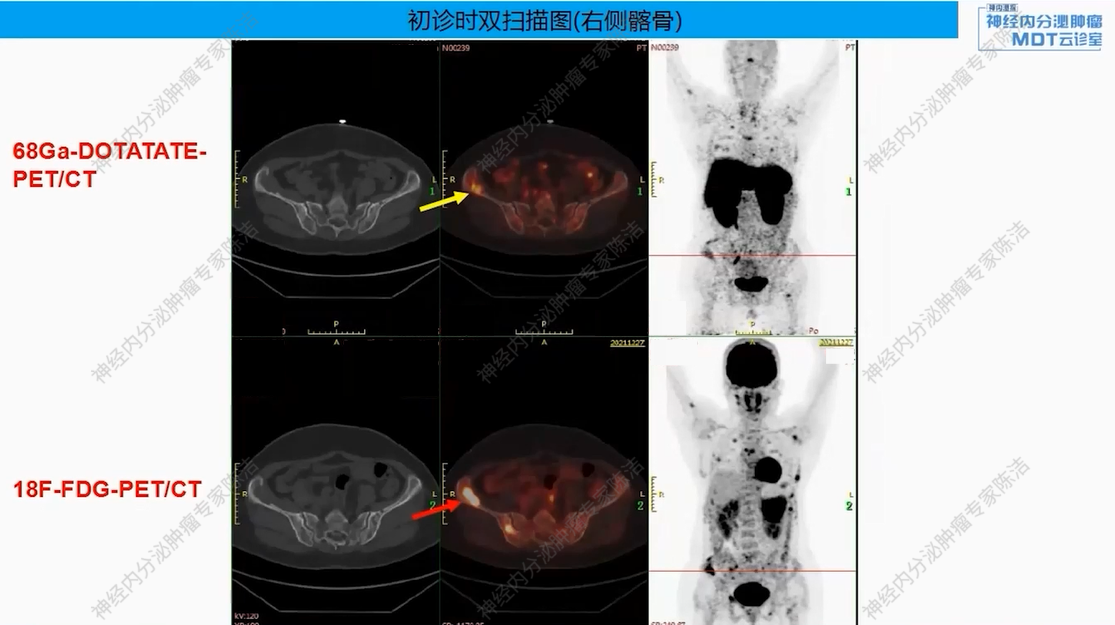

18F-FDG-PET-CT提示:胰尾部见巨大肿物(约8.6*7.2*7.8 cm),FDG代谢明显增高。胰体部另见一小结节(约0.8*0.7 cm),FDG代谢轻度增高。全身多发骨质改变,FDG代谢增高。

68Ga-DOTANOC-PET-CT提示:胰尾部巨大肿块,DOTANOC摄取阴性;胰体部小结节,DOTANOC摄取阳性。甲状旁腺区多发结节,DOTANOC摄取阳性;垂体区稍增大,DOTANOC摄取阳性。

核医学科徐俊彦教授:本病例双扫描PET显像体现了该患者多发肿瘤间异质性。胰尾大病灶(胰岛素瘤)呈SSTR阴性、FDG阳性,这符合约50%胰岛素瘤不表达SSTR的特征。而胰体小病灶呈SSTR阳性、FDG轻度增高。垂体区在SSTR(有生理性摄取)和FDG(无生理性摄取)上均呈阳性,提示垂体瘤可能。骨骼病灶呈SSTR和FDG“双阳性”,高度提示为SSTR阳性的NET转移,但建议对于骨病灶,可对相对表浅的病灶行骨穿以进一步明确骨病灶情况。从最初影像可见髂骨存在明显骨质破坏,甚至骨皮质整体受损,因此骨转移的可能性较大。然而,鉴于该患者同时患有甲状旁腺瘤,甲状旁腺瘤常伴发棕色瘤改变,故目前不能排除甲状旁腺继发的骨改变的可能。

该患者以低血糖为首发症状,影像学发现胰腺占位、甲状旁腺及垂体病变,并检测到MEN1胚系基因大片段缺失而最终确诊。胰腺上同时存在SSTR阴性的胰岛素瘤和SSTR阳性的神经内分泌肿瘤,且骨转移灶(SSTR阳性)极可能来源于后者(胰体小病灶),而非引起主要症状的前者(胰尾大病灶)。

后续治疗需要明确多发骨质改变的性质,建议对骨病灶进行穿刺活检。此举旨在鉴别其究竟是SSTR阳性的NET骨转移,还是甲状旁腺病变相关的骨病。若证实为SSTR阳性的NET转移,可考虑使用小剂量长效生长抑素类似物进行治疗。若证实为甲旁亢相关骨病,或活检未见肿瘤细胞,则无需使用生长抑素类似物。关于甲状旁腺处理,患者目前无明显血钙升高,可暂不手术,密切随访血钙、PTH变化。对于垂体处理,建议完善垂体薄层动态增强MRI以明确诊断,并评估对周围组织器官压迫情况。